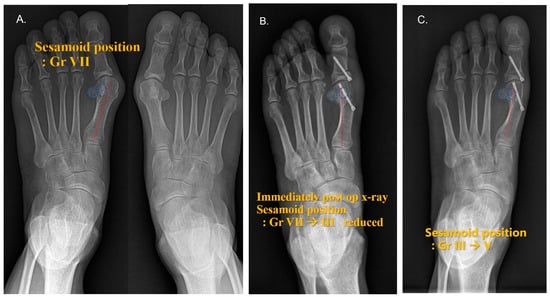

3.3. Medial Sesamoid Position

| DCMO (n = 30, 50%) | S.E.R.I. (n = 30, 50%) | |||||

| Grade | Pre-Operative | Early Follow-Up | Most Recent Follow-Up | Pre-Operative | Early Follow-Up | Most Recent Follow-Up |

| I | 3 (10%) | 1 (3%) | 16 (53%) | 7 (23%) | ||

| II | 10 (33%) | 5 (17%) | 4 (13%) | 3 (10%) | ||

| III | 9 (30%) | 6 (20%) | 5 (17%) | 8 (27%) | ||

| IV | 4 (13%) | 5 (17%) | 5 (17%) | 6 (20%) | ||

| V | 10 (33%) | 4 (13%) | 10 (33%) | 6 (20%) | 5 (17%) | |

| VI | 2 (7%) | 3 (10%) | 7 (23%) | 1 (3%) | ||

| VII | 18 (60%) | 17 (57%) | ||||

| DCMO (n = 30, 50%) | S.E.R.I. (n = 30, 50%) | p value | ||||

| Grade difference | ||||||

| Pre-op to early follow-up | −3.4 ± 1.1 | −4.4 ± 1.4 | 0.003 * | |||

| Pre-op to most recent follow-up | −2.4 ± 1.5 | −3.3 ± 1.7 | 0.028 * | |||

| Early to Most recent follow up | 1.0 ± 1.0 | 1.1 ± 1.2 | 0.822 * | |||

| Laterally displaced sesamoid | ||||||

| Pre-op | 30 (100%) | 30 (100%) | 0.999 † | |||

| Early follow-up | 4 (13%) | 0 (0%) | 0.038 † | |||

| Most recent follow-up | 13 (42%) | 6 (20%) | 0.052 † | |||